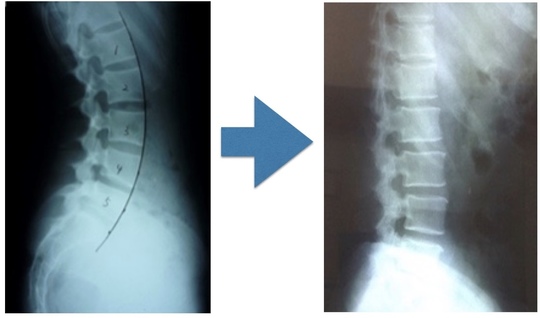

姿勢骨格分析画像検査

関節の動きを作る

腰痛は関節が癒着します

筋がギューと緊張すると関節の動きを阻害するし、痛みを繰り返すと関節は拘縮します。

関節の動きを制限することが、ぎっくり腰を起こす原因の1つになります。